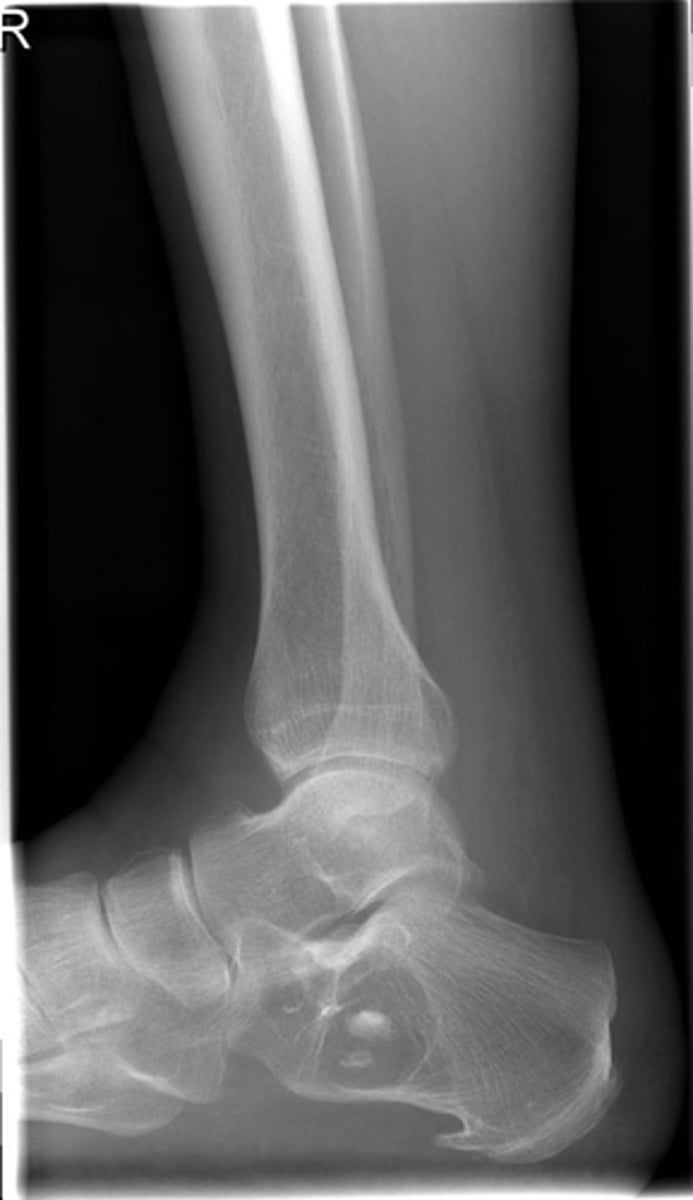

- Body of calcaneus

- Geographic

- Lucent

- Central target sequestrum

Describe the lesion

Intraosseous lipoma

Most likely diagnosis?

Refer to orthopedist or specialist

Next step?

Heel spur

What is going on with the posteroinferior calcaneus?

<p>What is going on with the posteroinferior calcaneus?</p>